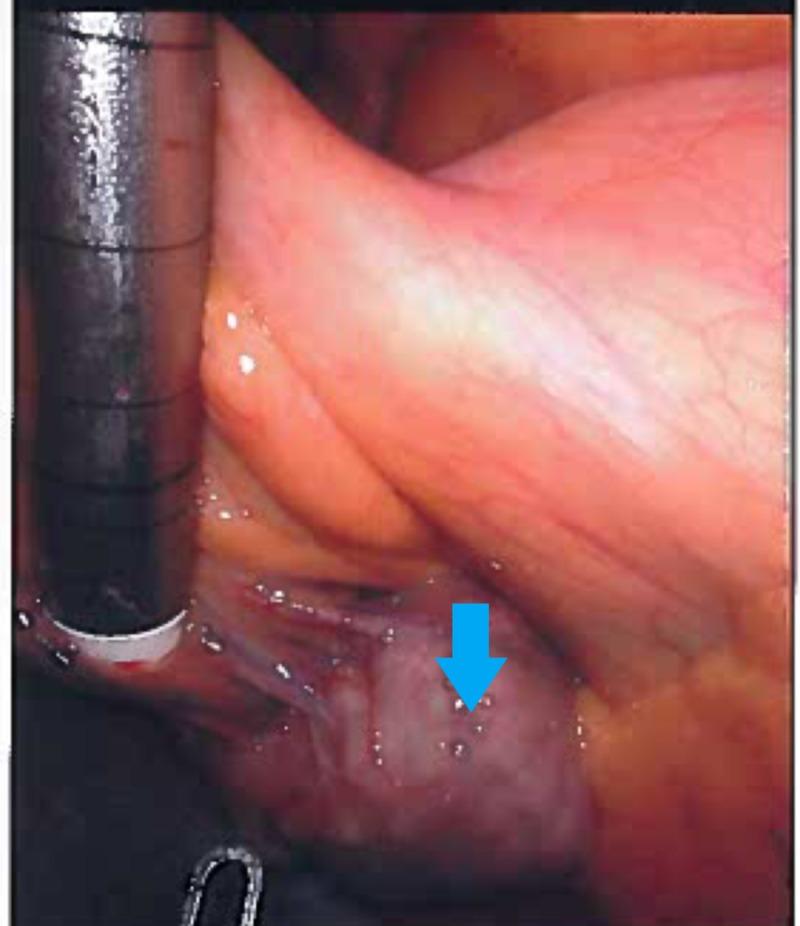

A rare case of a jejunal mesenteric pseudocyst treated by robotic resection is reported. A 25-year-old woman was admitted to our hospital with intermittent abdominal discomfort which was exacerbated by strenuous physical activities. Physical examination revealed a fluctuant mass without tenderness. Contrast-enhanced computed tomography revealed a 4 cm-sized non-enhancing heterogeneous mass on a proximal small bowel loop mesentery. Based on the findings, a differential diagnosis of a gastrointestinal stromal tumor, hematoma, desmoid tumor, and mesenteric cyst was made. Robotic diagnostic laparoscopy was performed to obtain an accurate diagnosis and treatment. Exploration of the cavity revealed a 4 cm fairly mobile mass originating from the mesentery of the jejunum. Segmental resection of the jejunum and its mesentery, including the mass and extracorporeal anastomosis, was performed without any complications. Macroscopically, the mass was cystic and the lumen had grumous material. The final pathological diagnosis was a mesenteric pseudocyst. The patient had an uneventful postoperative course.

报道了一例采用机器人切除术治疗空肠系膜假性囊肿的罕见病例。一名25岁女性因间歇性腹部不适入院,剧烈体育活动会使不适加剧。体格检查发现一个有波动感的肿块,无压痛。增强计算机断层扫描显示在近端小肠袢系膜上有一个4厘米大小的无强化的不均匀肿块。根据这些发现,对胃肠道间质瘤、血肿、硬纤维瘤和肠系膜囊肿进行了鉴别诊断。进行了机器人诊断性腹腔镜检查以获得准确的诊断和治疗。探查腹腔发现一个4厘米大小、相当活动的肿块,起源于空肠系膜。对空肠及其系膜进行了节段性切除,包括肿块和体外吻合,未出现任何并发症。肉眼可见,肿块为囊性,腔内有凝块状物质。最终病理诊断为肠系膜假性囊肿。患者术后恢复顺利。